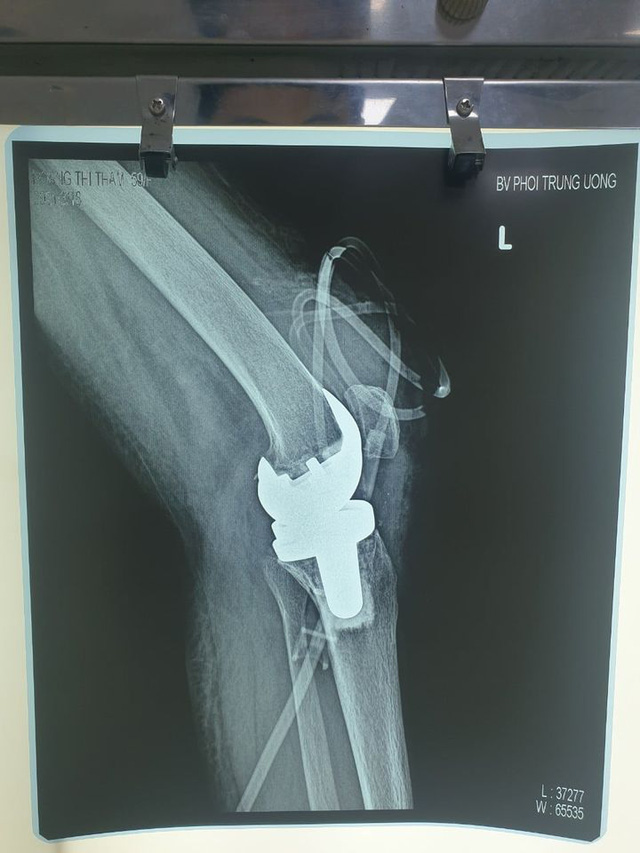

Đây là trường hợp người bệnh bị lao khớp gối đầu tiên tại Việt Nam được phẫu thuật thay khớp gối nhân tạo thành công.

Bà H.T.Th (59 tuổi, xã Tân Việt, Yên Mỹ, Hưng Yên) đã 17 năm chung sống với bệnh viêm khớp dạng thấp, mỗi năm đều đặn 3-4 lần phải lên bệnh viện Bạch Mai khám và lấy thuốc điều trị uống hàng ngày, bệnh có cải thiện tốt, bà đi lại và sinh hoạt cá nhân được. Khoảng 6 tháng trước khi vào Bệnh viện Phổi Trung ương, bà Th xuất hiện đau khớp gối bên trái, ban đầu bà nghĩ là đó là do bệnh viêm khớp dạng thấp mạn tính của bà, kèm theo cơn đau chưa dữ dội nên đã chủ quan, không khám xét kĩ. Bệnh tiến triển nặng dần, khớp gối bên trái của bệnh nhân ngày càng sưng to, đến khi đau nhiều, không đi lại được, khớp gối vỡ rò mủ mới đến bệnh viện Phổi Trung ương. Bệnh nhân tâm sự rằng, một phần do chủ quan, một phần do không có kiến thức về bệnh lao khớp nên bà Th đến viện khi bệnh đã ở giai đoạn muộn, các cơ vùng đùi đã teo, khớp đã cứng, không đi lại sinh hoạt được, khớp rò mủ liên tục khiến các cháu nội ngoại không dám đến gần bà nữa. Tâm lí chán nản vì bệnh tật, các cháu xa lánh, lúc đó bà Th. thật sự tuyệt vọng, việc di chuyển lại bình thường với bà là một điều không dám mơ ước. Nhưng điều kỳ diệu đã đến với bà khi được đội ngũ bác sĩ khoa Ngoại Tổng hợp, Bệnh viện Phổi Trung ương tiến hành phẫu thuật thay khớp gối thành công. Tháng 1/2021, sau khi bị sưng, đau rất nhiều tại khớp gối trái, bà Th. lên khám tại bệnh viện Bạch Mai, sau đó được chuyển sang bệnh viện Phổi Trung ương và được xét nghiệm dịch khớp gối phát hiện dương tính với vi khuẩn lao. Ngay lập tức, người bệnh đã được điều trị thuốc lao đa hóa trị liệu, chụp Cắt lớp vi tính thấy khớp gối bị phá hủy, có nhiều mủ áp xe. Các bác sĩ đã hội chẩn, quyết định thực hiện phẫu thuật làm sạch khớp gối, song song với điều trị đa hóa trị liệu.

Cho tới tháng 3/2021, người bệnh nhập viện theo hẹn khám lại, sau khi thăm khám và thực hiện các xét nghiệm thấy tình trạng viêm giảm nhiều, chụp phim đánh giá không còn áp xe khớp gối nữa, các bác sĩ khoa Ngoại tổng hợp quyết định phải tiến hành phẫu thuật thay khớp gối nhằm giúp cho người bệnh có cơ hội trở lại sinh hoạt bình thường. Ca phẫu thuật kéo dài 135 phút được thực hiện trong môi trường vô khuẩn tuyệt đối với độ chính xác cao. Sau khi phẫu thuật, tình trạng sức khỏe người bệnh ổn định, sau 2 ngày được tập phục hồi chức năng ngay, người bệnh có thể gấp duỗi khớp gối trong phạm vi nhất định, so với trước mổ khớp gối bị cứng, hầu như không gấp duỗi được. Sau hơn 1 tuần, người bệnh đã có thể bước đi những bước đầu tiên mà không cần sử dụng dụng cụ hỗ trợ, không cần người dìu dắt.

Theo Tiến sĩ, bác sĩ Nguyễn Khắc Tráng – Trưởng khoa Ngoại tổng hợp, bệnh viện Phổi Trung ương, phẫu thuật thay khớp gối bằng khớp nhân tạo là một phương pháp tiên tiến giúp bệnh nhân phục hồi gần như hoàn toàn chức năng vận động của khớp. Chỉ định thay khớp gối nhân tạo đa số do thoái hóa khớp, ngoài ra còn chỉ định trong trường hợp chấn thương làm hỏng khớp, các bệnh lí viêm khớp – màng hoạt dịch làm hỏng sụn khớp. Đối với lao khớp gối, cho đến nay quan điểm một số nước trên thế giới cũng như một số bệnh viện ở nước ta là không thay khớp. Có một số lí do, thứ nhất việc phẫu thuật thay khớp do lao là rất khó khăn do vi khuẩn lao phá hủy xương nhiều, không như trong bệnh lí thoái hóa chủ yếu tổn thương vùng sụn ở bề mặt, phần xương phía dưới còn khá nguyên vẹn nên việc thay khớp dễ dàng hơn nhiều. Thứ hai, lao là bệnh lí nhiễm trùng nên một số quan điểm rất ngại đặt dụng cụ nhân tạo. Thứ ba, trong lao khớp gối thì việc điều trị thuốc lao là yếu tố quyết định thành công. Trong lao xương khớp nói chung, nếu phát hiện sớm và điều trị kịp thời người bệnh có thể khỏi hoàn toàn vừa không để lại di chứng gì. Tuy nhiên người bệnh đến với chúng tôi chủ yếu là ở giai đoạn muộn, khớp đã bị biến dạng và phá hủy nhiều, trước đây đa phần đều làm phẫu thuật hàn cứng khớp - Tiến sĩ, bác sĩ Nguyễn Khắc Tráng cho biết thêm.